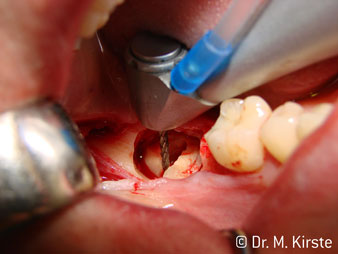

Die Winkelwahl des 45° Handstücks bringt viele Vorteile in der Anwendung. Chirurgisch tätige Kollegen, und für diese ist das Handstück in erster Linie entwickelt worden, werden schnell bemerken, dass man sehr gezielt arbeiten kann. Insbesondere bei der Weisheitszahnentfernung (Abb. 2) bedarf es keiner großen Weichteilabspreizungen im Wangenbereich (Abb. 3). Die Handstückkopfgestaltung kombiniert mit leichten Kopfdrehungen bei der Präparation lassen ein sicheres und schnelles Arbeiten im retromolaren Bereich zu.

Die professionelle Lagergestaltung im Innenleben des Handstückkopfes garantiert einen ruhigen Lauf der Bohrer, bei der Zahn- oder Wurzelseparation (Abb. 4 - 9) zeigt sich ein beeindruckendes Schnittbild ohne Schlageffekte.

Abb. 2

Abb. 3